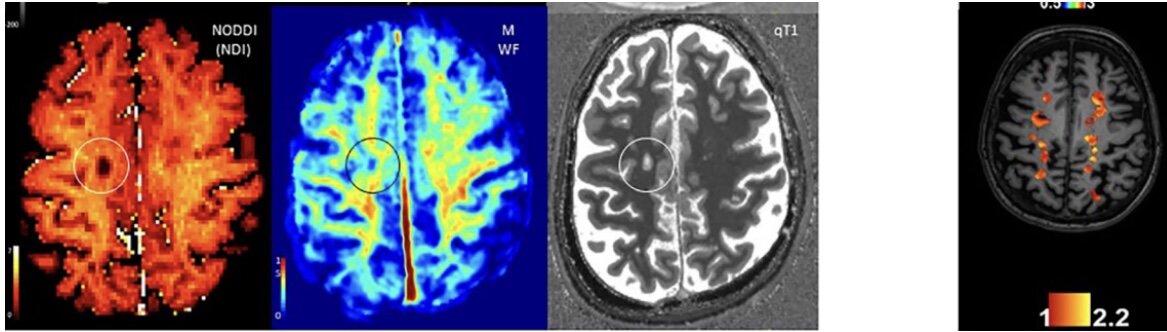

В последние годы в этом направлении начали вестись научные исследования, получены первые результаты по МРТ и биомаркерам (анализам крови на определенные вещества, в частности на уровень нейрофиламента https://stopsclerosis.ru/neirofilamenti/), показывающие, что у таких людей происходит постоянное повреждение головного мозга, но не в виде новых очагов или обострений, а путем совершенного нового, ранее неизвестного механизма. И вот этот новый механизм рассеянного склероза будет требовать и иного подхода в выявлении (скорее всего, путем новых режимов МРТ и новых биомаркеров) и иного подхода в лечении.